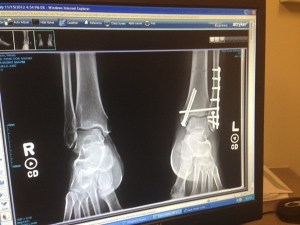

Poulsbo sergeant Wendy Davis' X-rays after her ankle surgery. Davis fractured her ankle and foot from a 'dangerous' obstacle during the Extreme K Mud Run Oct. 6.

Poulsbo sergeant sues Extreme K Mud Run organizers over injury

UPDATED: Wendy Davis, Poulsbo police sergeant and former deputy chief, filed a civil suit Dec. 19 with two…